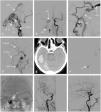

We report three cases of dural arteriovenous fistulae of the hypoglossal canal (HCDAVF) with different clinical and angiographic presentations and their treatment approach.